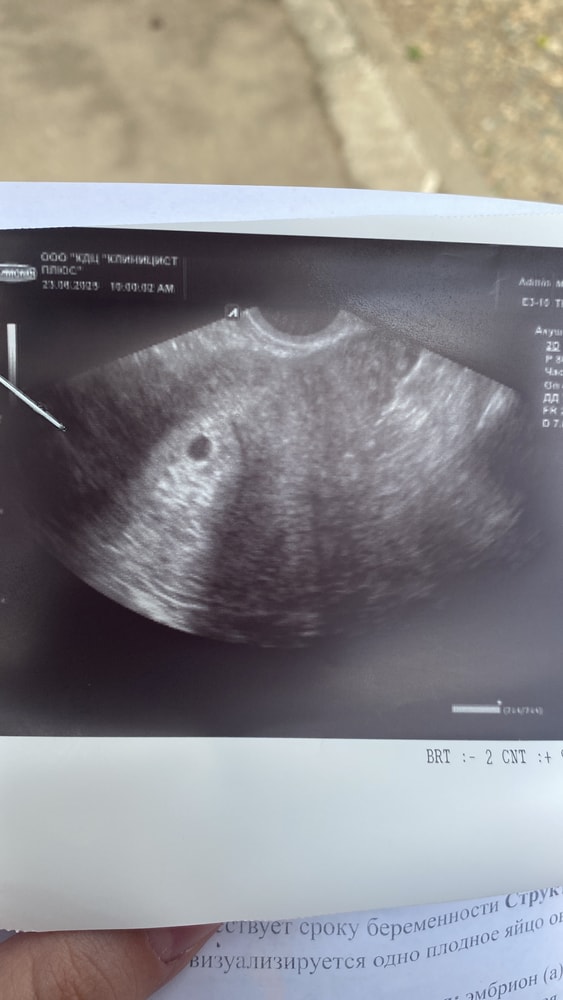

Первое узи- бусинка в матке)

Была на узи сегодня, нашли пя в матке,6-7 мм, совсем крошка еще. Через 2 недели пойду искать все остальное 🥰

Срок по месячным 5,4